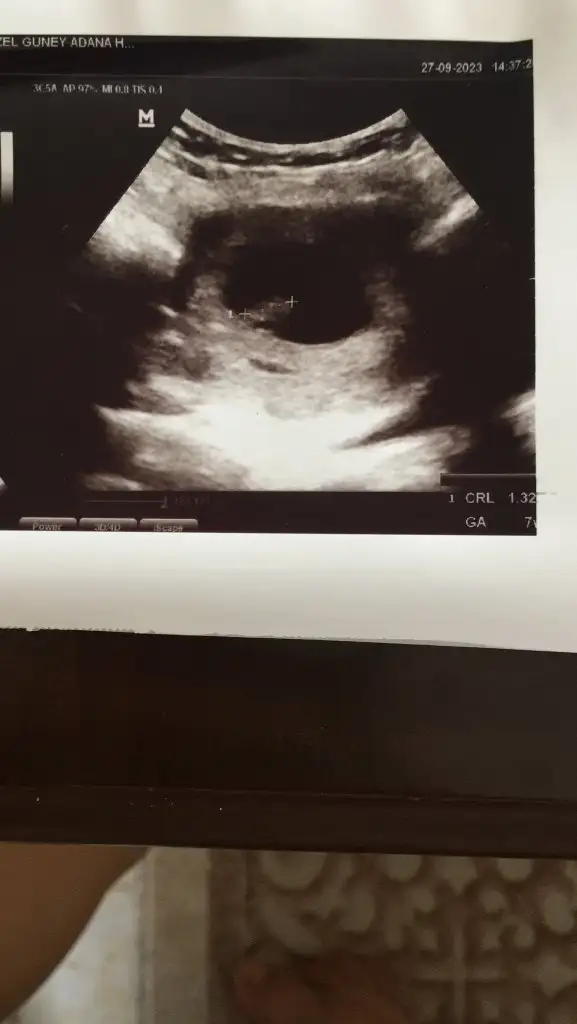

Bence kızEki Görüntüle 3295382 7 +3 haftalık cinsiyet tahmini

Ramzi teorisi okudum yüzde 97 dogruymuş.Ama neye göre bakcam ultrasona bilemedim. Size sormak istedim Bebeğim sağa daha yakın sanki bası da solda ayakları sağa bakıyor yani. Anlamadım ben. Sağlıklı olsun tabi kız erkek fark etmez ama merak ettim. İlk foto 5+5 iken 2.foto 9+3ken